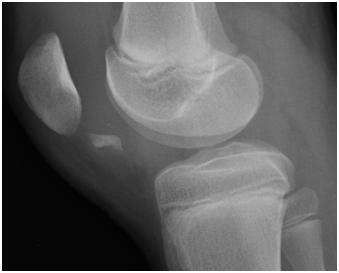

The knee radiograms revealed a free articular body that we interpreted as a possible osteochondral patella fracture (Figures 1 & 2).

Figures 1 & 2 AP and lateral radiograms: possible large inferior osteochondral patellar fragment, acting as a free articular body.